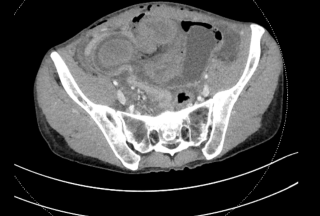

Case presentation

A 34 year-old postpartum patient developed acute abdominal pain, distension, and inflammatory syndrome on postoperative day 3 following cesarean section. Abdominopelvic CT revealed an incarcerated sigmoid loop herniating through the right broad ligament without signs of ischemia. An interdisciplinary discussion led to attempted endoscopic management with laparoscopic standby. Colonoscopy demonstrated a luminal stenosis corresponding to the herniation site, without ischemic changes. Gentle advancement of the endoscope combined with external manual pressure allowed complete reduction of the herniated segment. Full sigmoidoscopic reevaluation confirmed absence of ischemia. Surgical intervention was therefore avoided. Bowel function returned the following day, inflammatory markers normalized, and the postoperative course was uneventful. No recurrence or symptoms related to the ligament defect were observed during 8-month follow-up.